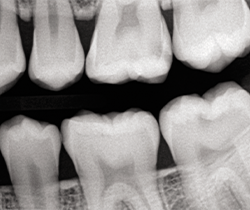

After occlusion is adjusted and restorations are finished and polished with OptraPol polishing cups and points (Ivoclar Vivadent), final radiographs and photos are taken to demonstrate the radiopacity of the material, the ideal interproximal contours and sealed margins, and its monolithic, void-free qualities (Figs. 16-20).

Fig. 20